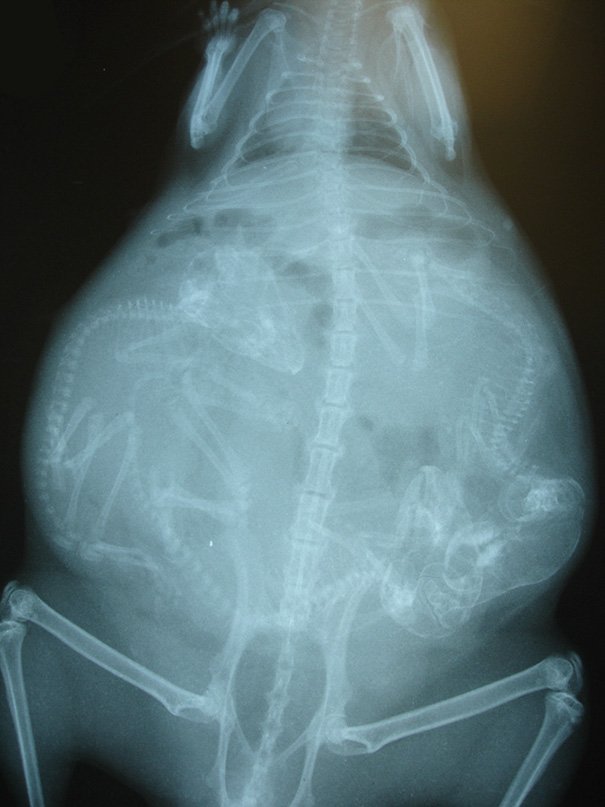

кошка